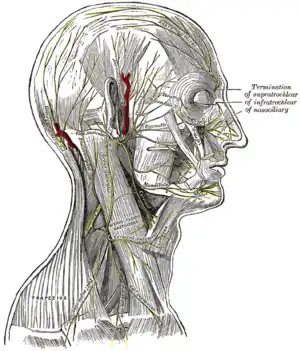

The internal carotid and vertebral arteries. Right side. The nerves of the scalp, face, and side of neck.

The nerves of the scalp, face, and side of neck. Side of neck, showing chief surface markings.